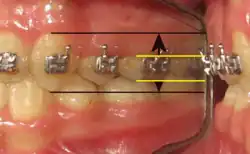

- 2. Stimulera les mécanorécepteurs périodontaux lors de l'intercuspidation maximale (Fig. 18) des 1500 à 2000 déglutition salivaire quotidiennes (« occlusion réflexe » et déglutition physiologique « en dents serrées ») ;

- Suivant l'Espace libre phonétique, l'épaisseur du REIOR varie de 3 à 6 millimètres. Au-delà de ces dimensions, il faut s'attendre à des fractures de cisaillement du matériau ou à un décollement du composite.

- L'analyse vidéographique numérique (voir « 6.2 Analyse fonctionnelle des signes » ci-avant) permet d'évaluer ces références physiologiques. Dans la déglutition atypique, l'espace libre est dysfonctionnel (trop grand). Corollairement, on estime la hauteur à ajouter aux dents naturelles pour obtenir un espace libre physiologique de 1,6 millimètre[6],[57],[58].

L'Espace libre physiologique est de ± 1,6 millimètre (B. Jankelson, A. Jeanmonod) et c'est une des composantes de la déglutition salivaire « en dents serrées » : élévations linguales dans le palais.

La déglutition atypique et ses interpositions linguales, ou étalements horizontaux, n'existent que lorsque cet Espace libre est largement supérieur à la norme, soit de 4 à plus de 10 millimètres.